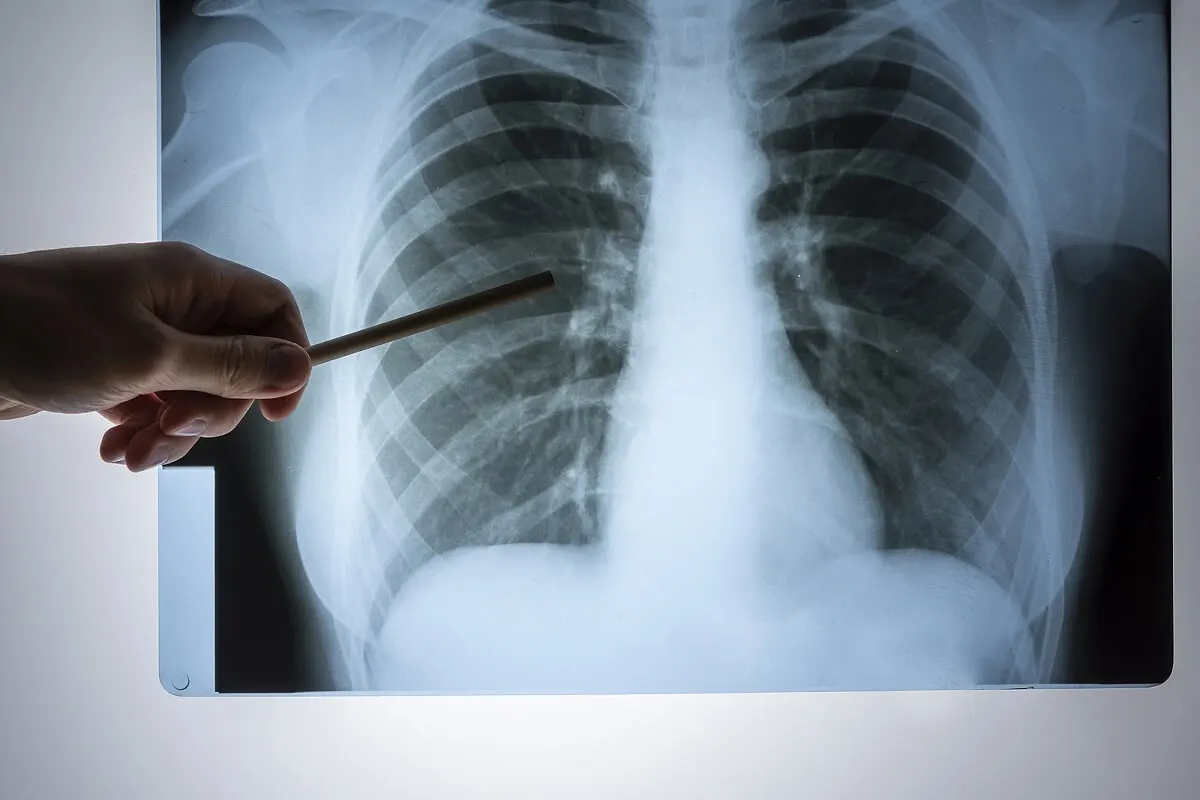

Neumonía derecha

Si el proceso infeccioso se localiza en el pulmón derecho, puede aparecer dolor en ese lado del tórax. Es necesaria una exploración física minuciosa y la realización de exámenes complementarios, con el fin de instaurar un tratamiento efectivo y oportuno.

Neumotórax derecho

La presencia de aire entre las capas de la pleura se conoce como neumotórax. Aunque un traumatismo puede ocasionarlo, otras posibles causas incluyen a ciertos procedimientos médicos e incluso a la ruptura espontánea de alguna zona de fragilidad en la pleura.

Con el neumotórax aparece dolor súbito en el lado afectado y dificultad respiratoria. El tratamiento depende de la gravedad del cuadro clínico.

Procesos tumorales como causas de dolor en el lado derecho del pecho

Los tumores ubicados en el pulmón derecho son otra causa de dolor torácico de ese lado. Sin embargo, cuando estos procesos se localizan en el tejido pulmonar, suelen ser asintomáticos en las etapas iniciales, debido a que no comprometen a la pleura parietal.